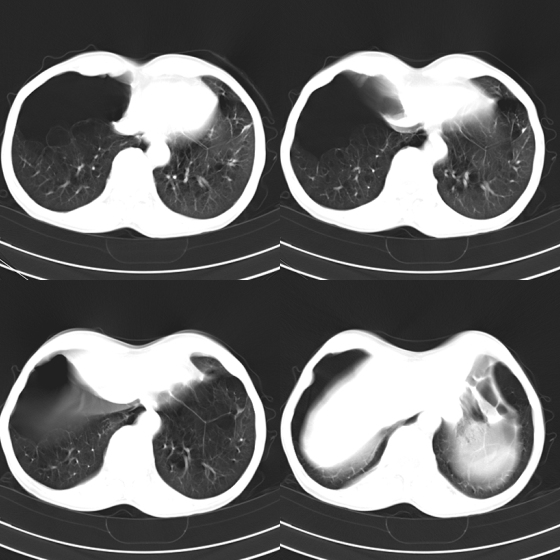

标题: CT21797:M65y,矽肺团块内空洞?

m65y,咳嗽、咯痰,煤工工作史10+年。低热,无明显脓臭痰。临床怀疑tb。

矽肺伴结核 右侧气胸,左肺上叶肺大泡

矽肺伴结核(左肺上叶病灶内空洞形成),右侧气胸,两肺多发性肺大泡。

考虑矽肺伴结核;

右侧气胸,左肺上叶肺大泡

考虑矽肺伴结核,右侧气胸,左肺上叶肺大泡。

告病重没有?这种气胸不易复张,咳嗽剧烈左肺大泡再破就难活了。煤尘肺常继发结核,影像学不易鉴别。有结核的可疑临床症状,ppd5u皮试阳性,特别是强阳性,就有诊断性抗痨治疗指针。不过排他性诊断是最重要的。左上空洞内液平就不是结核应有的。同意9楼楼主看法,同时注意合并感染的问题,抗炎覆盖广一点。